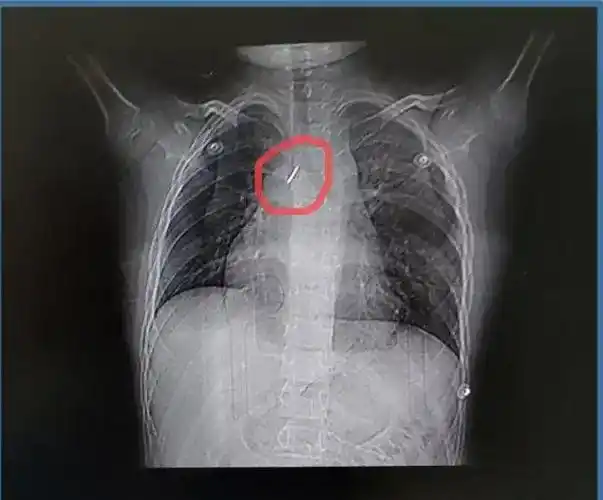

ct显示患者气管有异物.png

肺部ct显示,孩子的右下肺处有一高密度的异物影,将此处的支气管堵得严

经ct检查为支气管异物. 本文图片均为受访者提供

影像学检查发现了一片异物

74ct影像结果显示,异物所在的位置较深.

出现胸闷及呼吸困难,当地医院行胸片及胸部ct证实异物在右主支气管